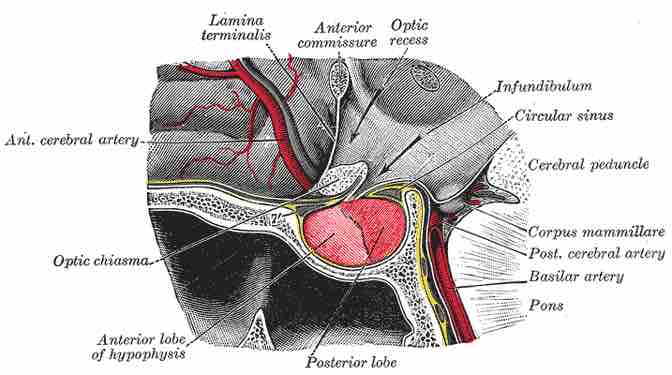

The pituitary gland

In this image, the pituitary gland is referred to by its other name, the hypophysis.